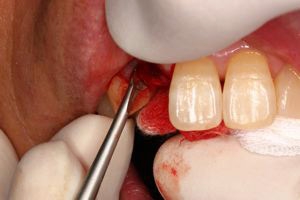

前歯即時埋入症例

術前術前主訴-前歯が腫れて痛い。治療法のうち、ブリッジとインプラントを説明して隣の前歯を削らないですむことからインプラントを選択された。 術前レントゲン術前レントゲン術前レントゲン 抜歯抜歯抜歯を行う。折れていた位置がかなり深い位置であるのがわかる。 歯根も抜歯歯根も抜歯

歯根も抜歯歯根も抜歯歯根も抜歯 抜歯した穴をよく掃除抜歯した穴をよく掃除抜歯した穴をよく掃除(掻爬)後すぐにインプラントを埋入 埋入直後のレントゲン埋入直後のレントゲン埋入直後のレントゲン。上部に見えるのは抜いた歯を利用して両どなりの歯に接着して一時的に使えるようにした。 二次オペ時二次オペ時